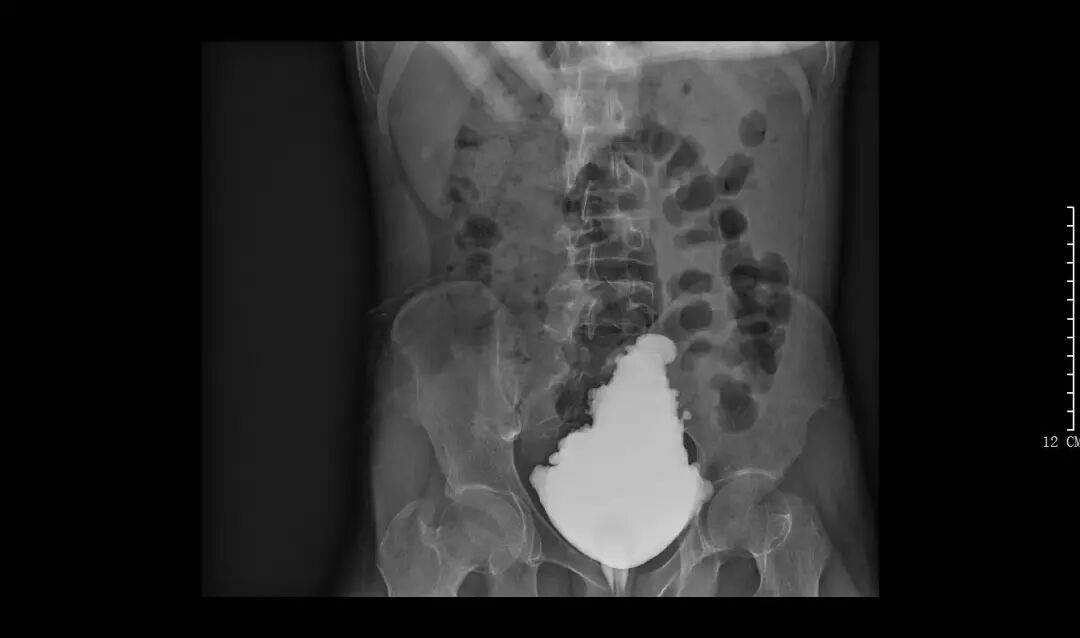

圖示:膀胱肉毒素注射后復(fù)查膀胱造影未見返流